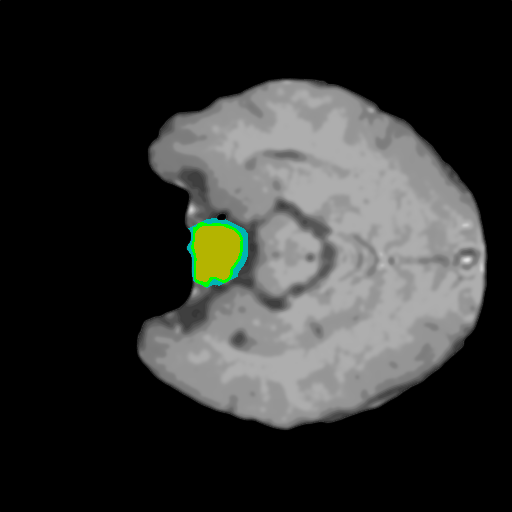

Extensive experiments have been performed in the current setup, and experimental outcomes are reported with the demonstration of numerical and statistical analyses using the proposed QFS-Net, QIS-Net [39], convolutional U-Net [18] and Residual U-Net (URes-Net) architectures [20]. The human expert segmented skull-tripped contrast enhanced DSC brain MR input image slices of size and ROIs are provided in Figure 5 as samples. The demonstration of QFS-Net segmented images followed by the essential post-processed outcome on the slice no. for class level with four distinct activation schemes () are shown in Figure 6. It is evident from the experimental data provided in Table LABEL:tab1 that the proposed QFS-Net performs optimally for the -connected quantum fuzzy pixel information heterogeneity assisted activation () with and gray scale set in comparison with other thresholding schemes and gray scale sets under the four evaluation parameters () [44]. The segmented tumors obtained using the proposed self-supervised procedure under class transition levels with four different thresholding schemes , , and are demonstrated in Figures 7- 8 for the class boundary sets and [39], respectively. The segmented images using the remaining two class boundary sets ( and ) [39] are provided in the supplementary materials section. The segmented ROIs describing the whole tumor region after the masking procedure using QIS-Net, U-Net and URes-Net are also reported in Figure 9.